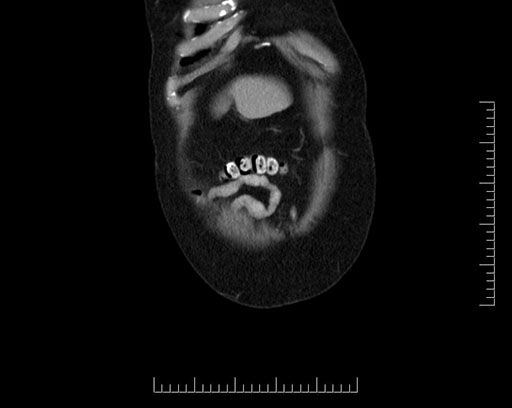

Imaging Analysis

Look through the patient's CT scan to identify any areas of concern for the necessary procedure.

Based on your CT findings, which issue(s) would give reason for "planned slowing down moment(s)" in this case?